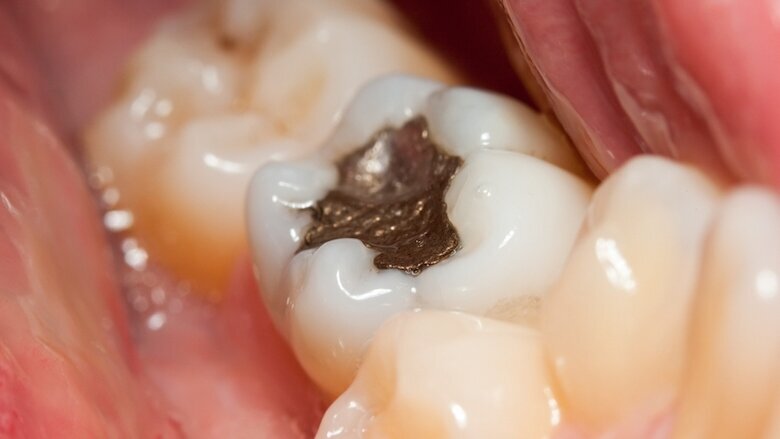

BRUSSELS, Belgium: Though fillings made with amalgam are generally considered to be safe for patients, studies have shown that dental amalgam may cause mercury poisoning in genetically susceptible populations. With this in mind, the use of dental amalgam fillings for pregnant and breastfeeding women, as well as children under the age of 15, has been banned (barring exceptional circumstances) as of 1 July 2018 in accordance with an EU regulation regarding the material.

Amalgam fillings have been an integral part of dental treatment for many years, although their use is declining in many high-income countries. However, there are currently no widely available alternatives in low- and middle-income countries. Amalgam is estimated to release up to 75 tons of highly toxic heavy metal in the EU annually.

Critics of amalgam have raised concerns about the health risks posed by the material during processing and disposal, as well as in the burning of deceased persons in crematoria. In addition, studies involving dental health care workers have indicated that mercury exposure from dental amalgam during placement and removal may cause or contribute to numerous chronic illnesses, and could lead to depression, anxiety and suicide.